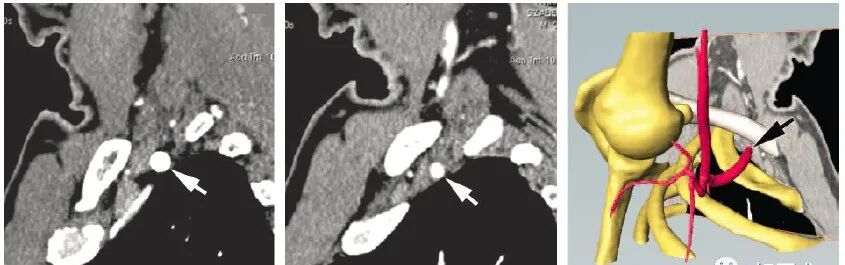

(二)病理 神经受压损伤常为假炎性肿胀样,感觉纤维最先受累,运动神经仅在晚期出现受压。此症状严重,较难恢复。神经受压时间过久则会通过交感神经导致血管舒缩障碍。锁骨下动脉血管壁可发生改变,动脉外膜增厚,间质水肿及同膜增厚伴管腔内血栓形成。早期血栓为纤维素血小板型,可出现雷诺(Raynaud)现象。 交感神经纤维收缩反射可加重指尖血管阻塞。 静脉在过度外展或内收时受到压迫,可观察到血液逆流停滞和外周静脉压上升,压迫消失后恢复正常。静脉壁反复损伤可发展类似炎症后纤维化样改变,静脉呈白色,失去半透明状态,且口径明显减小,形成侧支循环。早期发展趋势为静脉血栓,如侧支循环尚未形成,则可引起指端坏死改变。 临床表现 临床表现常见于中年妇女,20~40岁占80%,多有颈部外伤史。临床症状差异很大,且不持续 。分为神经受压和血管受压两类,神经受压的症状较为多见,也有神经和血管同时受压。 神经受压症状:有疼痛,感觉异常与麻木,常位于手指和手的尺神经分布区,也可在上肢、肩胛带和同侧肩背部疼痛并向上肢放射。晚期有感觉消失,运动无力,鱼际肌和骨间肌萎缩,4~5指伸肌麻痹形成爪形手。 臂丛神经受压:臂丛神经以跨越第1肋骨的下干最易受压,上干受压的较少,主要表现是臂丛神经下干受压的症状。 病人主要表现为:患侧肩部及上肢疼痛,无力,发病早期疼痛为间歇性,可向前臂及手部尺侧放射,肩外展及内旋时疼痛加剧。严重者可出现前臂及手部尺侧的感觉异常,甚至出现肌肉瘫痪,肌肉瘫痪及萎缩以小鱼际及骨问肌为甚,表现为爪形手畸形,有时也存在大鱼际肌及前臂肌肉肌力减退,锁骨上区有压痛并向前臂放射。 血管受压:一般病人不出现严重的血运障碍,当病变刺激血管时,可出现上肢套状感觉异常,患肢上举时感发冷,颜色苍白,桡动脉搏动减弱,锁骨下静脉严重受压时,则出现患肢远端水肿,发绀。血管严重受压时可出现锁骨下血管血栓形成,肢体远端血运障碍。 病史及症状: 既往史:大多数患者均有较长健康搜索的颈肩痛病史。 主要症状:本病的主要表现为颈肩部酸痛和不适,可向肩肘部放射患肢无力健康搜索,患者睡觉时患肢怎么放也不舒服可伴有头晕、耳鸣等症。 首诊时间:约30%的病例是在发病1年之内来诊,半数患者在1~2年来诊,另有20%患者超过2年来诊。 发病肢体:以非优势手多发,占2/3以上。 发病特点:急性发病者占55%慢性发病约占45%。 疼痛性质:均与体位关系密切,95%的患者呈间断性发作。 其他症状:几乎全部病例均有颈肩背部的异常、不适感约半数伴有疼痛。此外几乎95%的病例在睡觉时感到患肢怎么放也不舒服,同时伴有肩上举无力,少数患者可出现耳鸣、头昏及屈肘无力感。 诊断及鉴别诊断 1.诊断: 根据病史、局部体检、胸部和颈椎X线摄片和尺神经传导速度测定,一般可以明确诊断。 由于TOS患者临床表现复杂,与多种神经卡压症(如肘管)及运动神经元性疾病等症状相似,因此一种检查方法无法满足需要。 皮肤痛阈试验和两点辨别试验用于对中、晚期病人的诊断。而症状激发试验是最主要的早期诊断方法,包括“艾德森氏”试验、“过度外展”试验、“锁骨上叩击”试验、“上臂缺血”试验等。 1)“艾德森氏”征 病人端坐,双手置于膝上,将头转向患侧,下颌抬起使颈伸直,嘱病人深吸气后屏气,如桡动脉搏动减弱或消失者为阳性 2)“过度外展”试验 病人取坐位,检查者一手触摸病人桡动脉,同时将上臂被动地过度外展,如桡动脉搏动减弱或消失,腋下出现杂音者为阳性。 3)上臂缺血试验(一般认为最可靠) 即患者双上臂抬起,前臂屈曲90°,肩外展外旋,交替握拳与松开,若3min内一侧产生疼痛或不适而被迫下垂为阳性。 2.影像学 胸廓出口综合征主要依赖临床特征诊断,影像学有助于了解受压部位,解剖特征,确定手术方案:影像学检查X线颈椎片和胸片可以排除颈肋、第7颈椎横突过长、锁骨、第一肋骨畸形或其它骨性病。 平片——骨质异常 平片可以排除骨性结构的异常,图中两人都是临床证实的胸廓出口综合征的病人。 左图可以发现病人存在第七颈肋及颈七椎体横突过长; 右图则是锁骨骨折后骨痂过度形成而导致的肋骨锁骨间隙狭窄。 多普勒超声可以发现血管受压狭窄,血管造影可以确定狭窄和受压的部位: 评价动脉受压病变 静脉受压评估欠准确 臂丛显示不清 CT血管造影可用于评价动脉受压病变,图来自一个37岁的男性,图a是正常状态下的矢状位,锁骨下动脉没看到明显受压,图b是该病人手臂外展时的矢状位图,可以看到锁骨下动脉受压变窄,图cVR图直观显示血管跟周围骨骼结构的关系。值得注意的是,影像学对于静脉受压的评估相对欠准确,因为即使在正常人手臂外展时也会引起静脉受压,CT血管造影一个明显的缺点是对臂丛显示不清。 CT和MRI是一种敏感且无侵害性的方法,对TOS的确诊有一定帮助。 MRI--矢状位T1WI评价血管神经压迫最准确。 MRI可以准确观察与胸廓出口综合征相关的所有解剖结构,文献报道T1WI最有利于评估相关结构改变。这两幅图展示的是冠状位及轴位的T1WI图像。要注意的是,正常臂丛结构在所有序列上均为低信号。 相对于冠状位及轴位,矢状位对于评价血管神经压迫最准确。这是一个四十七岁的女性,左图是上臂外展前的T1WI矢状位图,臂丛没有受到明显压迫,而右图是上臂外展状态下的矢状位图,可以看到原先的结构明显受压。 电生理检查在TOS的早期无特殊价值,可能会出现F波延长,其它常常无异常发现。 晚期如尺神经运动传导速度在锁骨部减慢有较大的诊断价值。分别测定胸廓出口,肘部,前臂处尺神经传导速度。 正常胸廓出口为72m/s,肘部55m/s,前臂59m/s。胸廓出口综合征病人胸廓出口尺神经传导速度减少至32~65m/s,平均为53m/s。 3.辅助检查 上肢外展试验:上肢外展90°,135°和180°,手外旋,颈取伸展位。使锁骨下神经血管紧束压在胸小肌止点 下方和锁骨与第1肋骨间隙处,可感到颈肩部和上肢疼痛或疼痛加剧。桡动脉搏动减弱或消失,血压下降。 4.鉴别诊断 1)颈椎病 亦可出现上肢疼痛、无力、感觉异常,但颈椎病病人颈部常有压痛,压头试验及臂丛神经牵拉试验常为阳性。x线片有颈椎骨刺增生,椎间隙变窄,钩椎关节改变等退行性变的表现,CT及MRI可显示椎间盘变性及神经根、脊髓受压。 2)肘管综合征 为尺神经在肘管内受压所产生的临床综合征,表现为手无力,患肢手部尺侧感觉异常,小鱼际及骨间肌萎缩,爪形手,与本病主要累及尺神经所产生的临床表现相似,但前者无肩部症状,不波及正中神经,体征局限于肘部以下,AdSOn征、wright征、ROOs征等特殊试验阴性。 3)腕管综合征 为正中神经在腕管内受压所致,主要表现为手部桡侧2/3及桡侧3个半手指的感觉障碍,拇指对掌功能障碍,通过临床症状及检查,不难鉴别。 治疗 1.非手术治疗